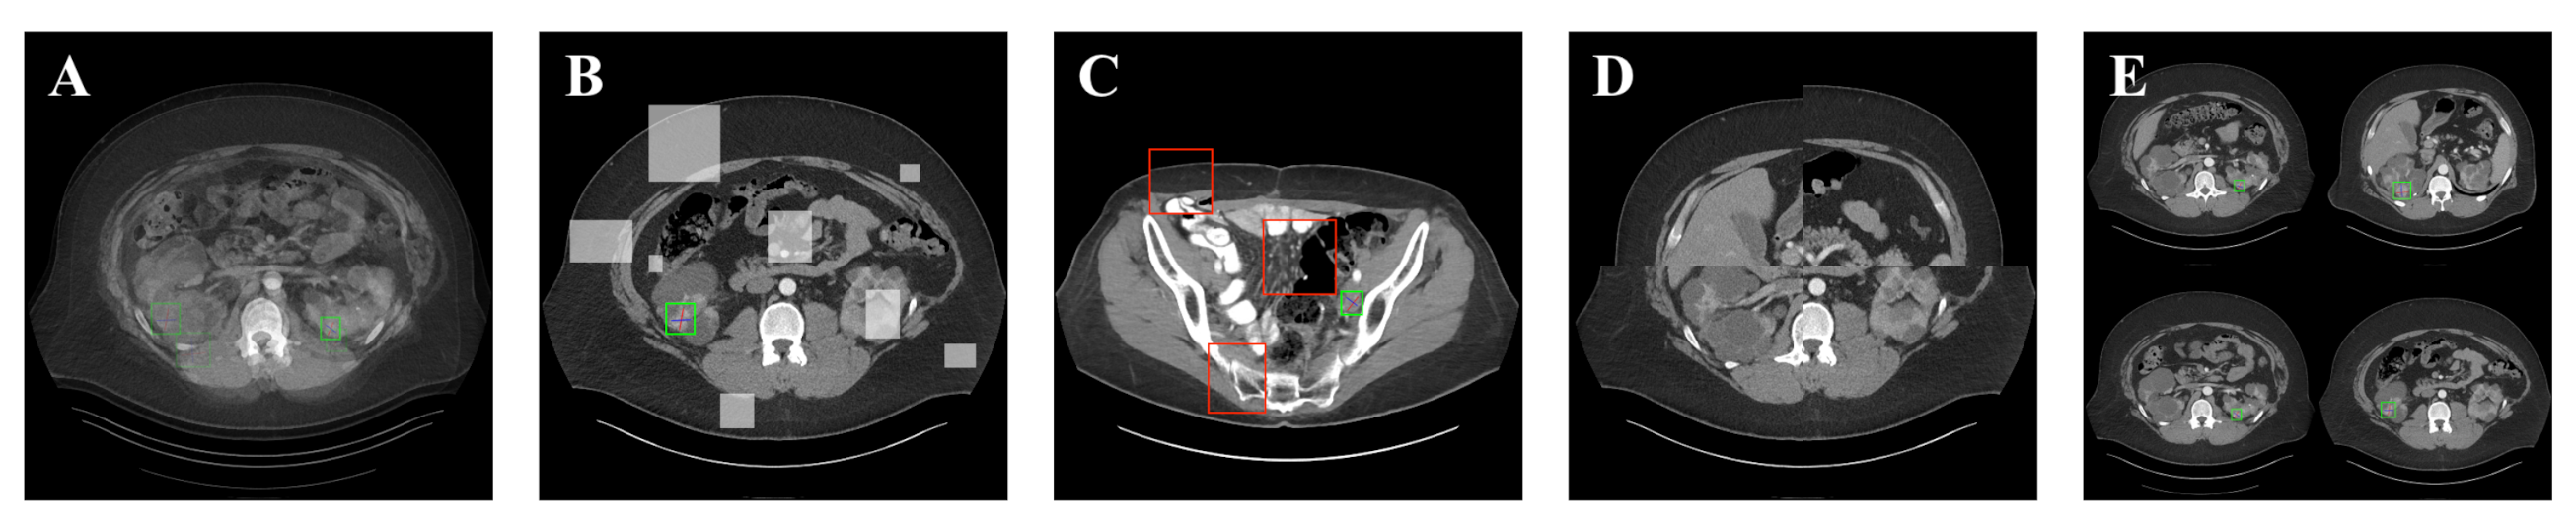

5.2. Detection Results

For further comparison, we extracted six images from the CT image series of DeepLesion. These images were taken from different sites of lesions and different areas of lesions, showing the detection results of the comparison model as comprehensively as possible. Figure 10, Figure 11, Figure 12, Figure 13, Figure 14, Figure 15, Figure 16, Figure 17, Figure 18 and Figure 19 show the detection results. All green boxes represent ground truth; red boxes denote predicted bounding boxes. It can be seen that Faster-RCNN performs very poorly on small lesions and lesions that are not easy to identify, while YOLO v3, YOLO v4, and SSD series perform relatively well. However, the aspect regression of the bounding box at small lesion locations is still not accurate. On the other hand, EfficientDet, Mask-RCNN, and YOLO v5 perform relatively well and detect lesions accurately. This may be related to the attention extraction module in these networks.

Figure 10.

The detection results of YOLO v3 in the DeepLesion dataset. The green box marks the location of the lesion.

Figure 11.

The detection results of YOLO v4 in the DeepLesion dataset. The green box marks the location of the lesion.

Figure 12.

The detection results of YOLO v5 in the DeepLesion dataset. The green box marks the location of the lesion.

Figure 13.

The detection results of Faster-RCNN in the DeepLesion dataset. The green box marks the location of the lesion.

Figure 14.

The detection results of Mask-RCNN in the DeepLesion dataset. The green box marks the location of the lesion.

Figure 15.

The detection results of EfficientDet in the DeepLesion dataset. The green box marks the location of the lesion.

Figure 16.

The detection results of SSD 300 in the DeepLesion dataset. The green box marks the location of the lesion.

Figure 17.

The detection results of SSD 512 in the DeepLesion dataset. The green box marks the location of the lesion.

Figure 18.

The detection results of SGDN 300 in the DeepLesion dataset. The green box marks the location of the lesion.

Figure 19.

The detection results of SGDN 512 in the DeepLesion dataset. The green box marks the location of the lesion.

Our model, especially SGDN 512, outperforms the previous models by detecting lesions with high accuracy for non-minimal lesions. Although there is still room for improvement, it has outperformed other models. On the one hand, we augment the image with the GAN model before it is fed into the backbone. On the other hand, we add the GAN model to the attention extraction module of the model, which can significantly improve the model’s robustness.

According to Figure 10, Figure 11, Figure 12, Figure 13, Figure 14, Figure 15, Figure 16, Figure 17, Figure 18 and Figure 19, the proposed model produces the most comprehensive detection results compared to other models. However, there are still a few cases where the shortcomings of SGDN can be seen: the arrows in Figure 19 show that our model is still not accurate at the edge of the lesion. In addition, from these figures, we can see that all the comparison models perform very poorly at the site of arrow A. The difference between the predicted box and the ground truth given by our model at arrow A is the largest compared to other recognition results.